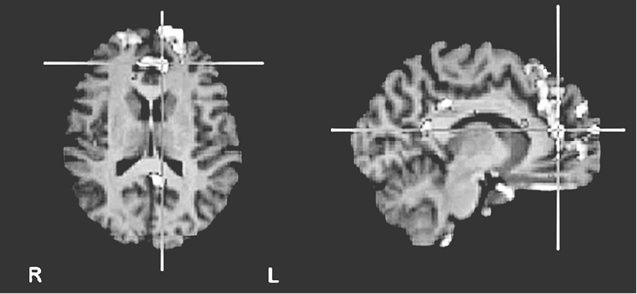

«Не уверен», как и предполагалось, активизировала переднюю поясную кору – своего рода нейронный сигнальный свет, вспыхивающий при внезапном появлении на горизонте чего-то нового и загадочного (рис. 8.1c (i) и (ii)).

Иллюстрация к книге — Флипноз. Искусство мгновенного убеждения [i_054.jpg]

Иллюстрация к книге — Флипноз. Искусство мгновенного убеждения [i_055.jpg]

Рис. 8.1c (i – вверху) и 8.1c (ii – внизу). Повышение активности во фронтальной части поясной извилины и в верхней лобной извилине при оценке утверждений, не поддающихся проверке («не уверен»). Рис. 8.1c (i) показывает разницу в активности по сравнению с картиной восприятия суждений, вызывающих доверие. Рис. 8.1c (ii) показывает разницу с картиной восприятия суждений, вызывающих недоверие (по материалам Харриса и др., 2008)